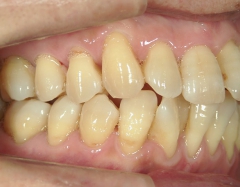

矯正歯科 治療前矯正歯科 治療前

矯正歯科 治療前

no.12_5333_治療前_左.jpgno.12_5333_治療前_正面.jpgno.12_5333_治療前_右.jpg